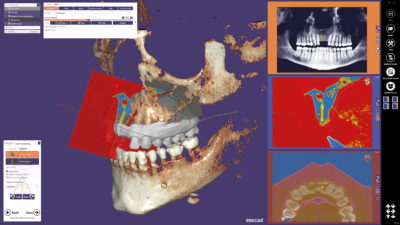

Le module Deltaface Aligner vous permettra la création de plaques occlusales transparentes.

Dans un premier temps, la segmentation des dents se fait de façon automatique. De même, le logiciel détecte automatiquement les collisions et génère ensuite automatiquement les étapes du traitement.

La numérotation et le positionnement des taquets sont tout aussi simples. Pour chaque étape, un modèle est créé par le logiciel et peut ainsi être imprimé en 3D. Ces modèles sont ensuite utilisés afin de créer des aligneurs transparents par thermoformage.

Puisqu'une image vaut mille mots, découvrez dès maintenant les fonctionnalités des nouvelles licences Deltaface :